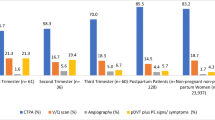

Of the 237 identified patients, 8 (3.3%) were excluded due to inadequate technical CTPA quality, and 229 patients were analyzed (mean age, 31.7 years; mean gestational age, 28 ± 7 weeks). The four different CT systems used over the study period had similar technical quality (p = 0.28). Of 229 patients 16 (7%) patients had PE, 144 (62.9%) had no abnormal findings, and 69 (30.1%) had an alternative diagnosis (consolidation, other pulmonary opacities, pleural effusion, and basal atelectasis). Gestational age, symptoms, and D-dimer levels were not significantly different between patients with or without PE (p > 0.05). Over time, radiation dose exposure decreased by 30% (p < 0.001), while the number of annual examinations increased by > 4-folds.

Of the 237 identified patients, 8 (3.3%) were excluded from analysis due to poor technical image quality. In 7 patients (88%), the pulmonary arteries were too poorly enhanced and in one patient, whose CTPA revealed left lower lobe pneumonia, there were too many respiratory artifacts. None of these 8 excluded patients underwent further diagnostic imaging, and they were thus considered negative for VTE. Our analysis included a total of 229 patients with a mean age of 31.7 ± 5.7 years (range 18–49 years), and a mean gestational age of 28 ± 7 weeks (range 6–40 weeks). Among these patients, 16 (7%) had acute PE, 69 (30.1%) had an alternative diagnosis, and 144 (62.9%) exhibited no abnormal findings upon CTPA (Fig. 1). Clinically, pulmonary infection with/without pleural effusion was diagnosed in 17 patients (24.6%), fluid overload with pulmonary opacities (mostly of cardiac, renal, or septic origin) with/without pleural effusion in 21 patients (30.4%), basal atelectasis (mostly due to immobilization or abdominal diseases) with/without pleural effusion in 21 patients (30.4%), pulmonary opacities of another origin (i.e., interstitial lung disease, ARDS) in 8 patients (11.6%), and pleural effusion only in 2 patients (3%). Figures 2 and 3 provide examples of acute PE with associated pulmonary infarction and pulmonary consolidation, thus pulmonary infection, in pregnant patients.

Table 2 presents the baseline characteristics, risk factors, medical history, symptoms, presence of ECG abnormalities, and D-dimer levels for PE-positive and PE-negative patients, with univariate comparison. None of the evaluated parameters significantly differed between the two groups. Chest pain was present in 93.8% of patients with PE, and 72.3% of patients without PE, but this difference was not statistically significant (p = 0.076). D-dimer levels did not significantly differ between the two groups (p = 0.91), as illustrated in Fig. 4.

Both CTDIvol and DLP significantly differed between the four different MDCT systems (p < 0.001), showing a significant decrease with newer systems (Fig. 5). On the other hand, the number of CT examinations performed annually showed a gradual and substantial increase, ranging from 4.8 scans per year with the 4-row CT system, to 21 scans per year with the 256-row system, constituting a > 4-fold rise over the last 17 years (Table 1).

This was the first study to evaluate the use of CTPA for suspected PE in pregnant women over a period of 17 years. Over this timeframe, we observed a dramatic increase in the number of scans performed, starting from 4.8 examinations per year in 2000, and reaching 21 examinations per year by 2018, mirroring the results from an extensive single-center review performed in North America [19]. In that cohort, the rate of X-ray imaging in pregnant patients increased by > 100% over 10 years, mostly due to the use of CT. In our cohort, however, the rate of PE-positive CTPAs did not simultaneously increase over time, being 11.4% from January 2000 to November 2002, 0% from December 2002 to January 2006, 6.8% from February 2006 to August 2015, and 11.1%. from September 2015 to August 2018. Thanks to technological improvements across the study period, the total radiation dose (DLP) decreased by 30% per scan, and CTDIvol dropped by almost 60%, from 11.5 to 4.8 mGy, without cutting back on image quality.